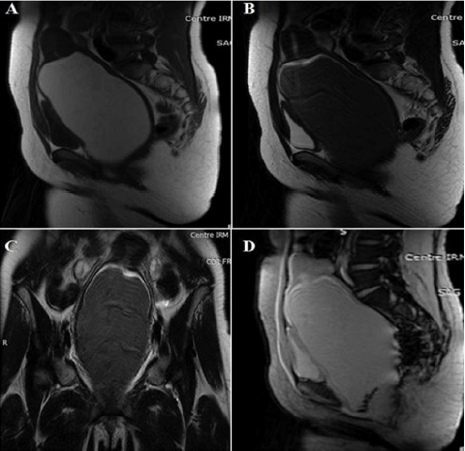

MRI takes place in the exploration of pelvic masses and uterovaginal malformations. These advantages are especially valid in the event of difficulty of ultrasound diagnosis. It is the best complementary exploration technique, giving the T2-weighted sequences a very good anatomical morphological analysis of the malformation. T1-weighted sequences confirm haematic content in the vagina and in the overlying uterine horn [26,27] (Figures 3 & 4). Congenital obstruction of the vaginal canal is a benign disease that progresses easily when properly diagnosed and treated. Ignorance of this pathology would expose to harmful complications: Urinary complications: Very common and often constitute a diagnostic circumstance. Acute urinary retention by urethral or bladder compression is often reported [30]. The distension involves the upper apparatus with ureterohydronephrosis. Infection is also reported due to stasis. Infection of vaginal retention fluid: It is a serious complication, which can be fatal and affect the fertility of patients. The vaginal infection can involve the uterine cavity with endometritis, which could progress to salpingitis, and finally pelviperitonitis. Upstream distension: The distension may involve the uterus with hematometry or hydrometry. At a more advanced stage, there is a hematosalpinx or a hydrosalpinx. Digestive complications: Rare, ranging from simple transit disorder to peritonitis by intraperitoneal passage of vaginal contents along the tubes or by rupture of a pyocolpos or rupture of the bladder [31]. Endometriotic transplants: This is a transplant of endometrial cells from menstrual tubal reflux into the pelvic peritoneum or ovary. Audbert reports a case of hematocolpos on hymenal imperforation with ovarian endometriosis and diffuse pelvic grafts [32].

Figure 4: Pelvic MRI

A. Sagittal SE T1 sequence

B. Sagittal sequence SE T2: significant distension of the vagina with T1 hypersignal content, T2 hypointense

C. SET2 coronal sequence: the collection continues up through the uterus. The ovaries are of normal size and morphology

D. Sagittal sequence T2 gradient echo: Presence of depressing deposits in T2 hypointense *related to hemosiderin.